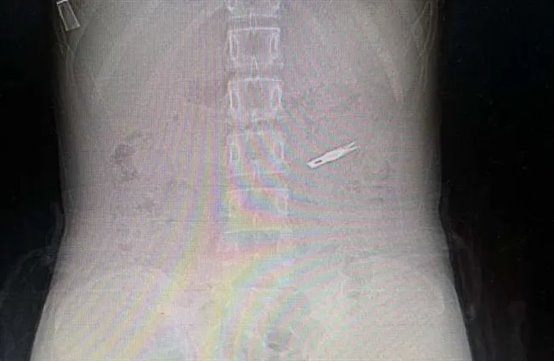

急救中心接诊医生紧急为其行腹部CT定位刀片位置,经过检查发现刀片已进入小肠。紧急呼叫消化内科医师进行急会诊,评估过后发现已无法经内镜下取出刀片。普外科二病区副主任任柯仔细研究CT图像并询问家属,发现小女孩体内刀片非常锋利,长度约3厘米,共两个刀片。“随着肠道蠕动,刀片每在体内多存在一分钟,肠破裂、肠出血甚至穿孔的可能性都在增加,另外还有扎破腹腔大血管引起大出血迅速危机生命的危险,每增加一秒,风险都在增加。”

刀片位置会随着肠道随时变换位置,腹腔镜下,任柯带领手术团队一边寻找刀片,一边一点点探查肠管是否被刀片划伤、划破。经过不懈的寻找,最终在小肠中上段找到了肠内的刀片,万幸的是没有造成肠道损伤。救治团队进行微创技术,将刀片成功取出,患者转危为安,腹部仅仅留下了2个1厘米的微孔。